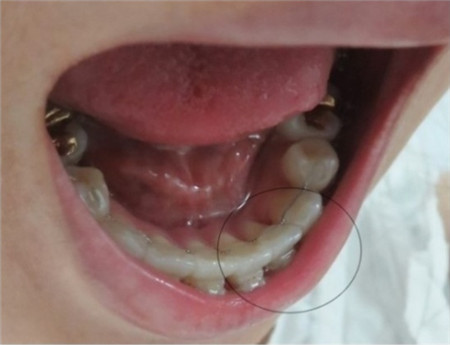

矫正15~23个月后,开缝的上排牙齿根部变化。

矫正开始后每个月都要去一次牙科进行月诊,3个月的功夫虎牙就变得整齐了,其他牙齿也开始移动,牙齿间的空隙慢慢闭合。这时候牙根没有闭合, 随着每次月诊时会重新调换并加紧弓丝的同时,牙根间的缝隙也很快就闭合了!之后就要使用橡皮筋。

现在可以看到上下牙齿正中线对齐呈一字型。其实以前比有虎牙更让我郁闷的是上下牙齿的正中线不对齐,矫正后现在已经完美。